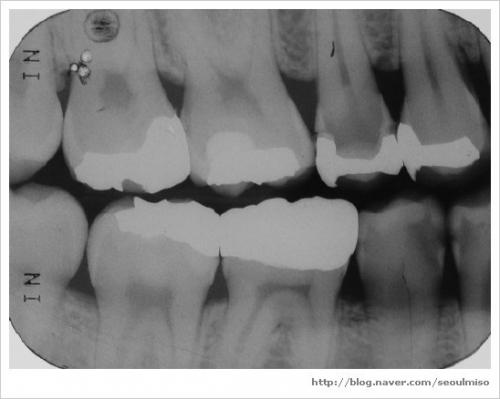

치아 사이의 충치를 제대로 확인하려면 교익 방사선 사진이 필요합니다.

( 추가: 파노라마 사진, 교익 방사선 사진 )